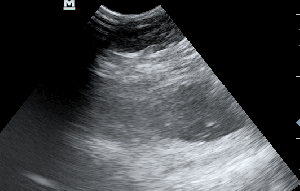

Η πάχυνση του τοιχώματος και η δοκίδωση του βλεννογόνου είναι εμφανής σε όλες τις εικόνες. Πολλές φορές οι λαγόνιοι λεμφαδένες μπορεί να είναι ήπια διογκωμένοι και να έχουν αντιδραστική ηχομορφολογία. Ο έλεγχος με έγχρωμο Doppler του τοιχώματος της άδειας κύστης μπορεί να μας δείξει ροή αίματος στα αγγεία της κύστης. Αντίθετα, είναι πιθανό, όσο η κύστη γεμίζει με ούρο η ροή αίματος να μην είναι ορατή με το Doppler. Αυτό συμβαίνει συχνά στη χρόνια βακτηριακή κυστίτιδα λόγω της ίνωσης του τοιχώματος της ουροδόχου και αυτή είναι μία από τις αιτίες της μη ανταπόκρισης στη θεραπεία. Η συγκεκριμένη παθοφυσιολογία έχει μελετηθεί στον άνθρωπο με την βοήθεια ενδοσκοπικού υπερήχου.

The increase of thickness of the urinary bladder wall and the striation of the mucosa is evident. Inguinal lymphnodes are usually prominent and mildly enlarged. Colour Doppler may reveal the blood flow of the mucosa of the empty urinary bladder, whereas the blood flow in a full bladder appears decreased. This could be because of the fibrosis of the urinary bladder wall and could explain why sometimes chronic conditions like these do not respond well to antibiotics. This pathophysiology has been studied in humans with the use of endoscopic ultrasound.